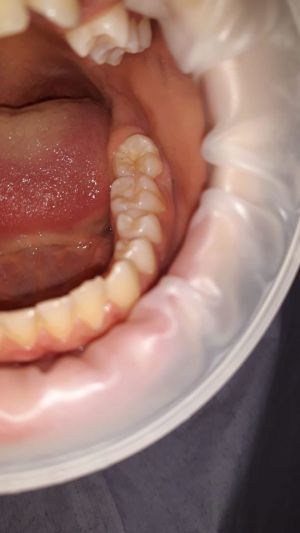

Le sigillature dei solchi e delle fessure sono otturazioni meccaniche che vengono effettuate per correggere le anomalie dello smalto dentario presenti nelle superfici masticatorie dei molari, dei premolari e, in alcuni casi, sulla superficie palatale dei denti anteriori impedendo alla placca batterica di penetrarvi dentro.

- 1. isolare il dente mediante l’utilizzo della diga, cioè un telo colorato in lattice necessario per isolare il dente oppure tramite rulli di cotone;